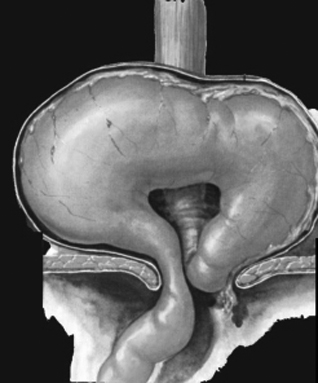

- Type IV correspond a une

hernie de l'estomac entierement en volvulus avant de oesophage

sus diapragmatique accompagnement parfoi avec de autre viscere ( intestin grele , colon ... )

Hernie hiatale type I ( hernie hyatale de

glissement ) |

|

Hernie hiatale type II ( type avec

estomac est enroulement sus diapragmatique .Le

cardia est en place |